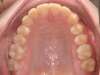

Absence congénitale des incisives latérales supérieures. Appareils fixes pour créer l’espace nécessaire à la mise en place de facettes en remplacement des latérales.

Après